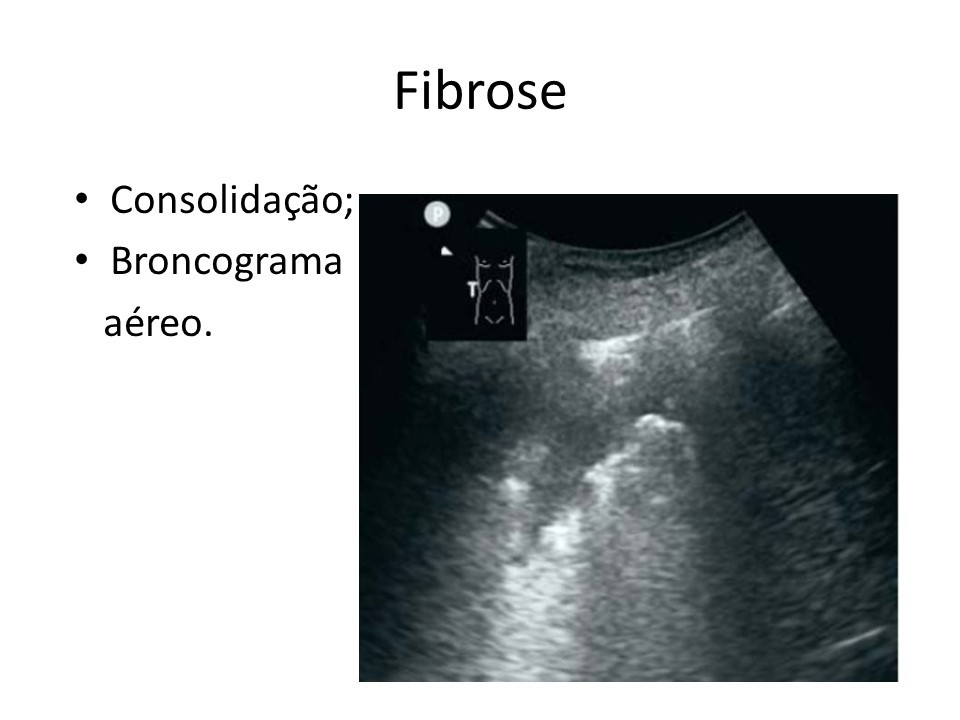

Home Imagem de ultrassom mostra marcas em pulmão com fibrose causada pelo coronavírus (Divulgação)